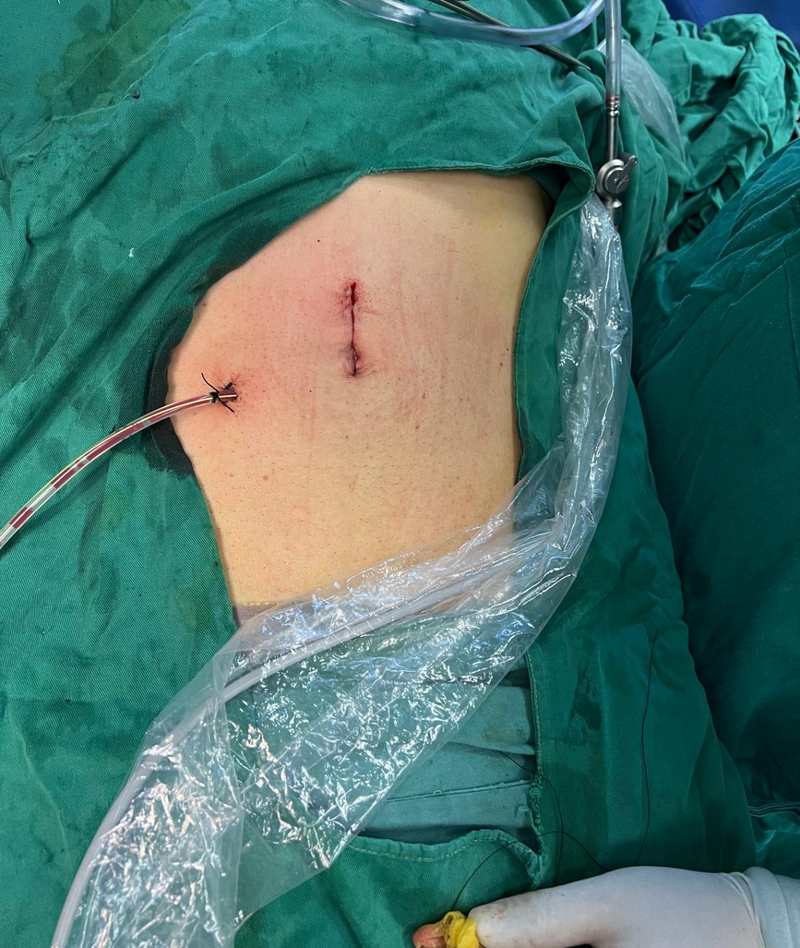

泌尿外科團隊積極完善術前檢查后,為其行經腹單孔腹腔鏡下雙側腎臟囊腫去頂減壓手術,手術歷時2小時,手術過程順利,術中無明顯出血,術后8小時患者腸道恢復通氣下床活動,第二天拔除引流管,術后第三天患者出院。

據悉,經腹單孔腹腔鏡手術通常是通過取腹部肚臍大約2-3cm切口,將傳統(tǒng)腹腔鏡多個穿刺孔匯集到臍部單一孔道,置入手術器械來完成手術,相比較傳統(tǒng)多孔腹腔鏡手術,腹部只有一個經臍部小切口,創(chuàng)傷更小,手術通道標本易于取出,便于處理大范圍病變,患者術后疼痛感更輕、恢復快、住院時間短,同時臍部皮膚皺褶可以遮蓋切口,愈合后疤痕幾乎不可見,從而達到無瘢痕手術目的,美容效果滿意。